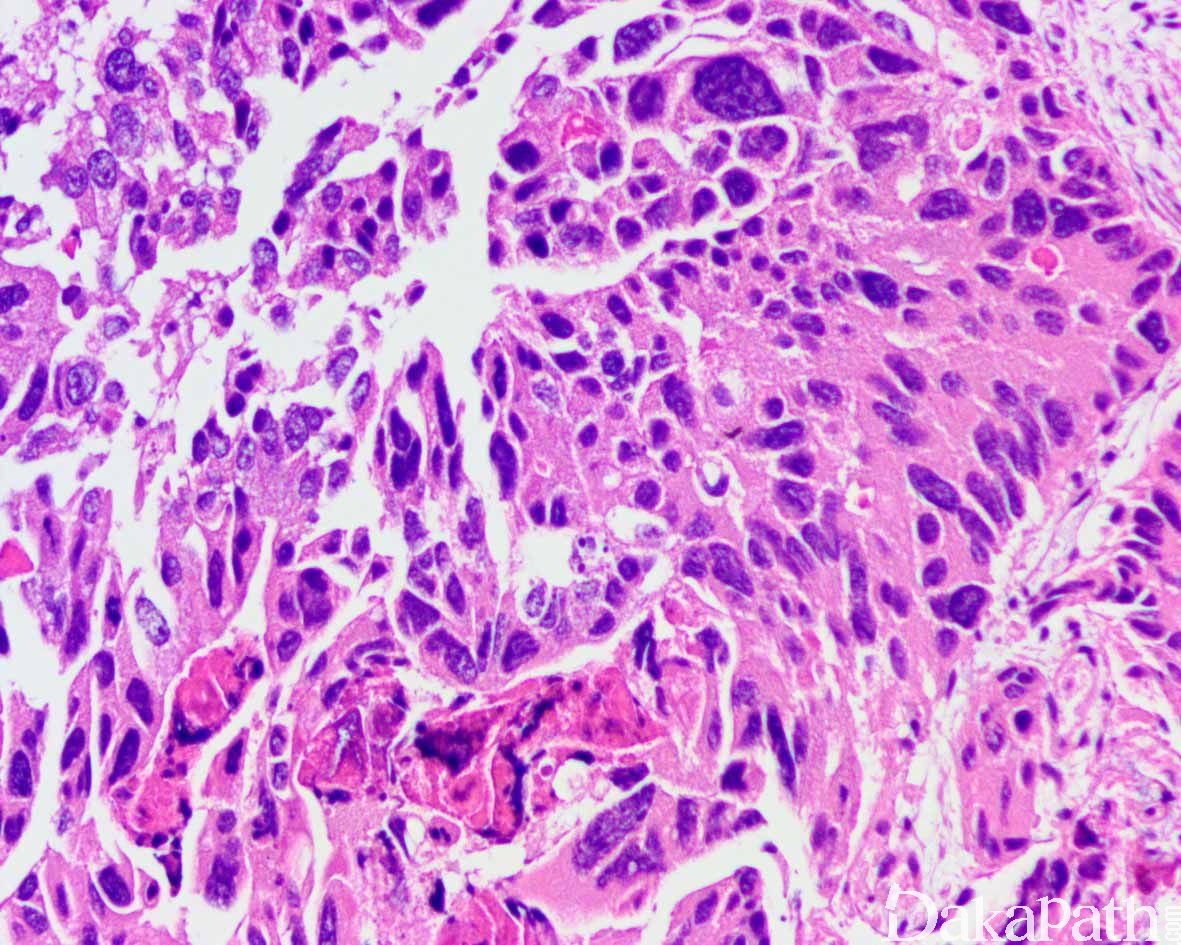

前列腺腺泡性腺癌,多形性巨细胞型

Acinar Adenocarcinoma,Pleomorphic Giant Cell Variant

特别罕见的前列腺癌亚型,瘤细胞瘤体巨大,具有多形性、间变性和怪异性的核,无梭形细胞成分。

比例从< 5%-70%不等,肿瘤具有巨大、怪异的间变性瘤细胞,具多形性核,核分裂象活跃,常见非典型核分裂象,但缺乏梭形细胞;

几乎总是和 ≥Gleason 9 的广泛普通腺癌混合存在;